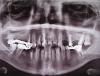

У меня во рту просто фильм ужасов. Зубного врача посещаю с раннего детства, но спасти зубы это не помогает, и с каждым годом ситуация становится всё хуже. Три года назад имела глупость поставить в Украине коронки с мостами (не помню,что за материал, но НЕ металлокерамика). Один мост отвалился через год, поставила его повторно и через пол года он снова упал. На днях упал и второй верхний мост. Врачи предлагают совершенно разные варианты, терапевт говорит,что лечить совершенно нечего и начиная с 5-к нужно всё удалять и ставить импланты, имплантолог сказал,что импланты положение не спасут и предлагает сначала исправить открытый прикус. У меня уже в голове полная каша и не знаю какое решение будет правильным. Посоветуйсте пожалуйста.

По предоставленной скудной информации Ваш план лечения примерно такой.

Удаление нескольких зубов.

Лечение и перелечивание нескольких зубов.

Установка нескольких имплантатов.

Комплексное протезирование всех зубов (ориентировочно 28 единиц).

Ориентировочное время лечения более 6-ти месяцев.